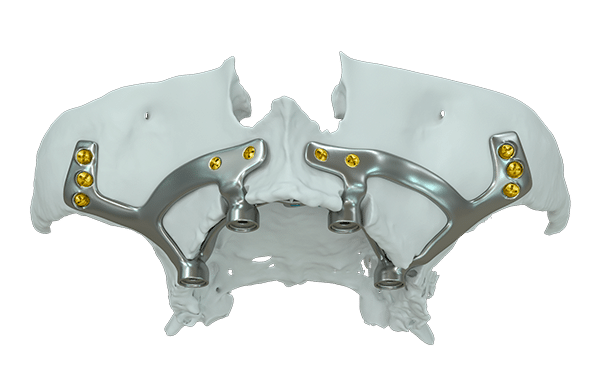

Design My Implants uses CT scans to create tailored bone reconstruction systems. Our titanium parts are finely polished and treated for optimal bone bonding. We strategically place the device and screws for maximum durability. The screws are set in the densest bone areas for secure fixation. Our entire process emphasizes precision for lasting results.

Rigorously Validated Design

Each design undergoes structural analysis using finite element methods, confirming the implant’s ability to withstand the various forces it will encounter in the mouth.

Titanium Construction for Biocompatibility

Made from titanium, a material known for its strength, durability, and biocompatibility, it ensures the body accepts the implant with minimal risk of reaction.